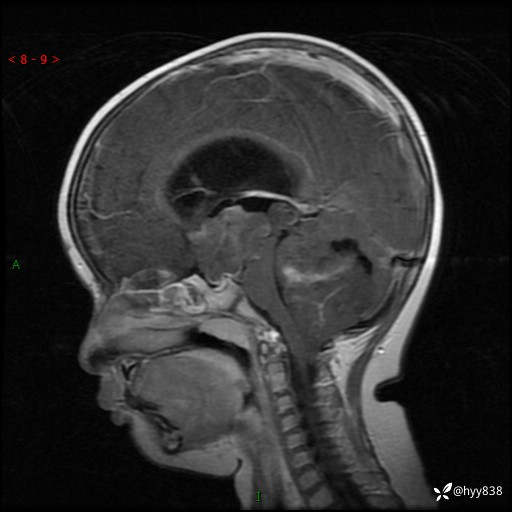

性别:女

年龄:3岁

简要病史:发现行走不稳2个月,加重1个月

颅脑MRI平扫+增强

三脑室、四脑室多发病变,如何分析?